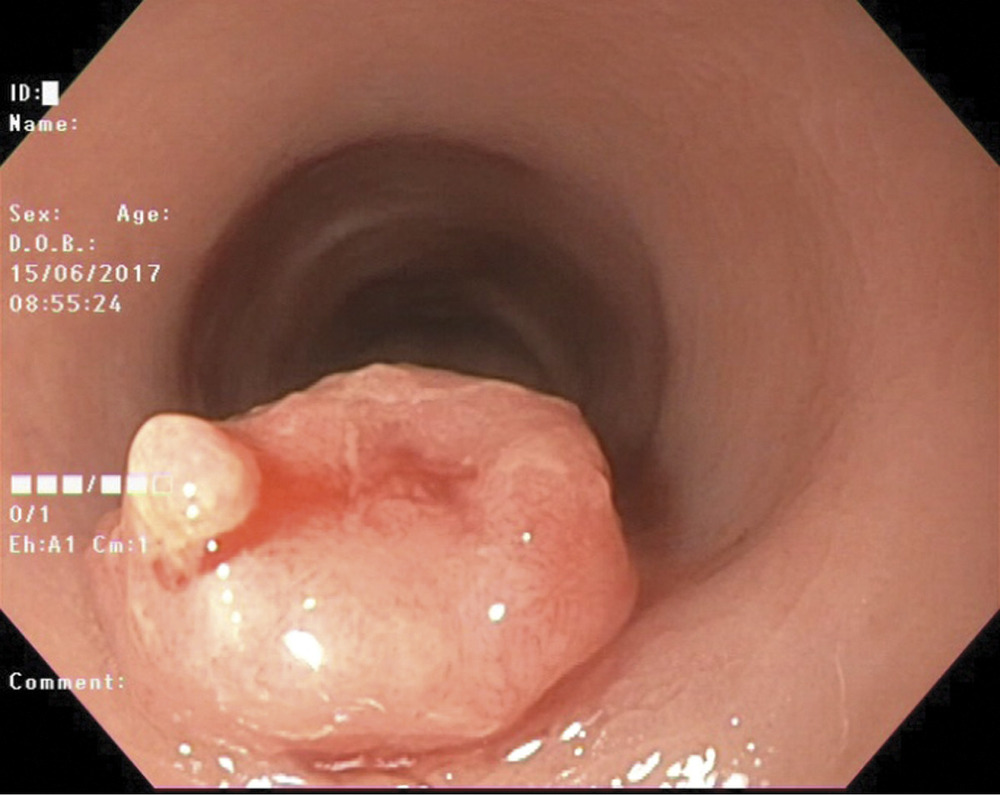

Пациентка К., 59 лет. Диагноз: рак сигмовидной кишки T1N0M0, 1-я стадия, 2-я клиническая группа. При обследовании пациентки в проксимальной части сигмовидной кишки выявлена полиповидная эпителиальная опухоль размером 2,5×2,0 см (рис. 1)